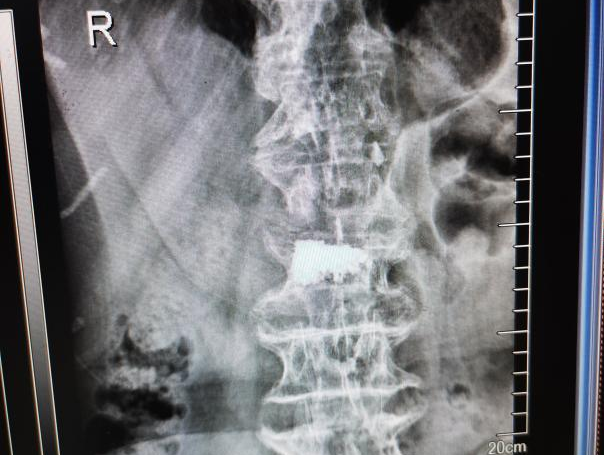

2025年11月1日,由遵义市医学会手外科分会主办、遵义市第二城市医疗集团(贵州航天医院)承办的遵义市医学会手外科分会学术交流会暨贵州省继续医学教育项目《急诊手外伤治疗临床研究新进展专题研讨班》在贵州航天医院成功举办,汇聚了遵义市手外科领域专家及基层医疗骨干,通过专题研讨与临床经验分享,共探急诊手外伤诊疗新进展。 会议特邀遵义市医学会手外科分会主任委员金文虎教授,遵义市医学会手外科分会副主任委员张子阳教授,遵义市医学会手外科分会常务委员杨绍浦教授,贵州航天医院陈明勇教授、赵兴东教授等遵义市手外伤专家进行交流分享;贵州航天医院党委委员、副院长彭亮参加会议并致辞,贵州航天医院骨科医务人员,遵义市第二城市医疗集团成员单位及红花岗区、绥阳县、桐梓县等区县医疗机构手外伤骨干参与。 贵州航天医院党委委员、副院长彭亮致辞 学术交流 本次学术交流以“急诊手外伤治疗临床研究新进展”为主题,通过理论授课与临床案例结合,共同探讨急诊手外伤临床诊疗全链条诊疗策略、关键技术、临床研究新进展,促进规范化诊疗技术向基层下沉,助力提升区域手外伤应急处置与修复能力。 贵州航天医院赵兴东教授分享《急诊手外伤的诊断与治疗原则》 贵州航天医院陈明勇教授分享《开放性骨折的治疗原则》 贵州航天医院张军教授分享《甲沟炎Winograd手术的临床应用》 贵州航天医院赵兴东教授分享《手部常见的皮肤缺损及治疗原则》 贵州航天医院张艳金教授分享《开放性骨折的清创术》 贵州航天医院冷家雄教授分享《下肢创面修复的常用皮瓣之股前外侧皮瓣》 贵州航天医院邬夏荣教授分享《踝关节慢性不稳的诊治》 贵州航天医院卢懿明教授分享《掌骨骨折》 贵州航天医院张艳金教授分享《手部肌腱的解剖与修复方法》 本次研讨班为遵义市手外科领域医务人员提供了深度交流契机,强化了医疗机构间的协作网络,进一步推动学科创新与临床实践融合,为健康遵义建设注入新动能。 贵州航天医院骨科专家简介 陈明勇 骨一科主任,副主任医师 临床擅长:从事创伤骨科工作约20年,对骨缺损、骨不连、骨肿瘤、肢体畸形等的肢体矫形重建及功能重建,慢性化脓性骨髓炎的根治治疗、糖尿病足的保肢治疗、快速康复理念(ERAS)下的老年骨折的诊治,四肢复杂骨折的诊治,四肢骨折等微创手术治疗具有丰富的临床经验。 2004年毕业于遵义医学院临床专业,曾在中国人民解放军总医院、广西医科大学第一附属医院、上海第六人民医院骨科进修。中国中西医结合学会骨伤科专业委员会横向骨搬移治疗糖尿病足及微血管网再生学组首届委员,遵义市医学会创伤分会常务委员。 瞿 晖 骨科党支部书记,骨二科主任,副主任医师 临床擅长:对骨科的常见病、关节外科、脊柱外科及运动医学疾病的诊治具有丰富的临床经验,熟练掌握骨科手术操作技术。 毕业于遵义医学院临床医学系,2005年前往广州中山大学第一附院骨显微医学部进修学习,2011年前往成都华西医院进修学习,并多次在省内外学习骨科相关知识,是中华医学会骨科分会会员。 赵小锋 中共党员,骨二科副主任,副主任医师 临床擅长:从事骨科临床工作11年,对骨科常见病、多发病诊疗有较为丰富的临床经验,擅长脊柱相关疾病诊断及治疗,尤其是颈、腰、腿疼痛疾病诊断及治疗,擅长胸腰椎骨折微创经皮穿刺内固定术、经皮穿刺椎体成形术、经皮穿刺脊柱内镜下腰椎间盘摘除术、单纯开创腰椎间盘摘除术、腰椎滑脱复位椎间植骨椎融合内固定术、腰椎管狭窄减压融合内固定术及人工髋、膝关节置换术等。 2012年毕业于遵义医学院外科学专业硕士研究生,2019年参加“遵义市115医学人才精英计划”于上海交通大学第一附属医院培训学习,2023年于北京大学第三人民医院脊柱外科进修学习,曾获得遵义市优秀医师荣誉称号。 遵义市手外科第一届委员,遵义市医学会创伤分会第一届委员,遵义市医学会创伤分会第二届委员,贵州省康复医学会第三届脊柱脊髓专业会委员,遵义市医学会烧伤与整形外科学分会委员,发表论文5篇,其中国家级核心期刊1篇,SCI论文1篇,主持市级课题1项并结题,参与市级课题2项。 赵兴东 骨科主任医师 临床擅长:擅长骨科的常见病及各种创伤、四肢骨折创伤修复、骨感染、手足疾病的诊治和手足体表畸形的矫形整复,熟练掌握骨科四肢骨病及创伤的手术操作技术,尤其在四肢关节复杂性损伤、手足外伤、组织缺损创面、难治创面的皮瓣修复方面及平足、高弓足矫形方面及四肢慢性疼痛诊治、康复方面具有丰富的临床经验。 硕士研究生,毕业于遵义医学院临床外科系,2015年前往山东省立医院手足外科进修学习;遵义市医学分会创伤分会第一、二届委员,遵义市手外科医学会第二委届员会常务委员;在省级及省级以上期刊发表文章9篇,参编著作2部,参与主持并完成市级课题1项,参与市级课题2项、省级课题1项。 张艳金 中共党员,骨科副主任医师 临床擅长:从事骨外科工作16年,对复合伤、多发伤的救治、四肢骨干骨折、关节周围骨折、骨肿瘤、骨髓炎等诊治具有丰富的临床经验。 中共党员,硕士研究生,2006年本科毕业于山西医科大学第二临床医学院,2011年研究生毕业于北京军区总医院;在“老年COPD患者合并髋部骨折的诊治”国际合作课题组研究两年,在老年髋部骨折的诊治方面具有丰富的经验,并发表论文6篇;主持遵义市级课题1项,承担遵义医科大学的临床教学工作,获得遵义医科大学优秀带教老师荣誉。编撰有《骨科疾病诊疗精粹》一书,开展2项新技术,编撰地方规范《务川自治县创伤骨科常见疾病诊疗规范》一书。 张俊凯 骨科副主任医师 临床擅长:从事骨科临床工作28年,对创伤骨折、骨感染、骨缺损、骨不连等外科诊治,四肢骨折的微创手术治疗,四肢复杂骨折(如关节内粉碎性骨折、多发骨折等)的损伤控制及手术治疗等具有丰富的临床经验。 1995年毕业于遵义医学院临床专业,2009年前往复旦大学附属医院骨科进修1年。 卢懿明 中共党员,骨科副主任医师 临床擅长:从事骨科工作18年,对创伤骨折、四肢骨折的微创手术治疗、四肢复杂骨折(如关节内粉碎性骨折、多发骨折等)的损伤控制及手术治疗,尤其是髋部骨折的PFNA等微创技术,踝关节骨折、膝关节周围骨折的Mipo微创技术等具有丰富的临床经验,开展了4项新技术,发明6项新型专利技术。 2005年毕业于遵义医学院临床专业,2017年,前往南方医科大学第三附属医院骨科进修半年,回院后运用Mipo技术对骨干骨折及干骺端骨折的治疗技术,同时积极开展骨盆骨折、髋臼骨折腹直肌外侧切口的应用;发表了多篇专业论文,经常参与省内外学术交流会授课,获得医院荣誉称号多个。 邬夏荣 骨科副主任医师 临床擅长:从事骨科工作16年,对四肢复杂骨折、骨肿瘤的诊治,尤其是足踝创伤、慢性踝关节损伤、平足症等诊疗具有丰富的临床经验。 2006年毕业于遵义医科大学临床医学专业,曾在陆军军医大学西南医院进修学习,发表多篇骨科学术论文。 余德怀 中共党员,骨科副主任医师 临床擅长:从事骨科工作10余年,对运动医学、骨关节、脊柱外科常见病、多发病的诊治具有丰富的临床经验。 硕士研究生,2011年毕业于遵义医学院临床医学专业,曾前往遵义医科大学附属医院运动医学专业进修学习;是贵州省医学会运动医学分会青年委员,西部关节镜联盟委员;发表多篇骨科学术论文。 冯 乾 骨科副主任医师 临床擅长:从事骨科工作近20年,熟练掌握骨科多发病及常见病的诊治,尤其对脊柱退变性疾病的诊断及治疗具有丰富的临床经验,主要研究脊柱微创相关治疗方式,能熟练开展椎间孔镜及UBE。 曾前往北京大学第三医院进修学习疼痛及椎间孔镜、首都医科大学友谊医院专业进修脊柱内镜;是贵州省康复医学会第三届脊柱脊髓专业委员会委员;发明专利3项、发表脊柱外科专业论文多篇。 贵州航天医院骨科简介 基本情况 贵州航天医院(原3417医院)骨科组建于1968年,前身是以创伤和断肢(断指)再植闻名于世的上海市第六人民医院骨科,中国断肢(断指)再植的奠基者、中科院院士陈仲伟等专家莅临科室指导医疗和教学,并在70年代开展了贵州省首例断肢(断指)再植手术。组建50余年来,诊治患者已逾百万,挽救了无数的伤病员,成为了保障遵义地区人民群众健康的重要支撑。 经过几代人的不懈努力,今天的骨科,已由创伤骨科发展至骨病、骨肿瘤、骨结核等领域,现有脊柱外科、关节外科、四肢创伤、手足外科四个亚专科,成为了集医疗、教学、科研于一体的综合学科,是贵州省临床重点专科、遵义市临床重点专科、遵义市骨科临床医学中心、遵义市基层骨科专科联盟理事长单位。 科室目前开放床位110张,共有医护人员50余人,副高级以上专家18人,硕士研究生15人。拥有一流骨科医疗设备多台,每年不定期选派优秀技术骨干到全国各大知名医学院校进修、学习、参观、交流,并邀请国内、国外知名专家教授来院进行交流、指导,通过不断引进国内外先进的诊疗技术,科室医疗技术水平稳步提升,为广大人民群众提供了优质的医疗服务。 专科特色 骨一科 (一)骨缺损、骨不连的肢体与功能重建 胫骨横向骨搬移技术治疗糖尿病足: (二)慢性骨髓炎的根治治疗 (三)肢体缺血性疾病如糖尿病足、脉管炎的保肢治疗 (四)皮瓣修复 (五)复杂创伤的治疗 (六)老年髋部骨折及小儿骨折快速手术 老年髋部骨折: 骨二科 (一)胸腰椎骨折微创经皮椎弓根螺钉固定术 (二)老年性骨质疏松性患者腰椎滑脱脊柱内固定术(骨水泥螺钉) (三)V形双通道脊柱内镜技术(VBE)腰椎融合术治疗腰椎退行性疾病 (四)老年性骨质疏松性骨折(PVP/PKP)术 (五)人工髋关节置换术 (六)双侧股骨头坏死人工全髋关节置换 (七)右侧全髋置换术后假体周围骨折翻修 (八)人工膝关节置换术 (九)人工膝关节假体松动翻修 (十)关节镜技术 传统手术切口 关节镜技术切口 诊疗范围 骨一科 1.四肢创伤、矫形。 2.手、足踝外科。 骨二科 End